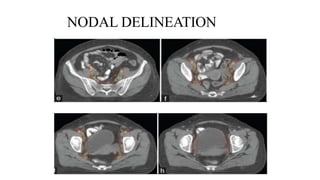

NODAL DELINEATION